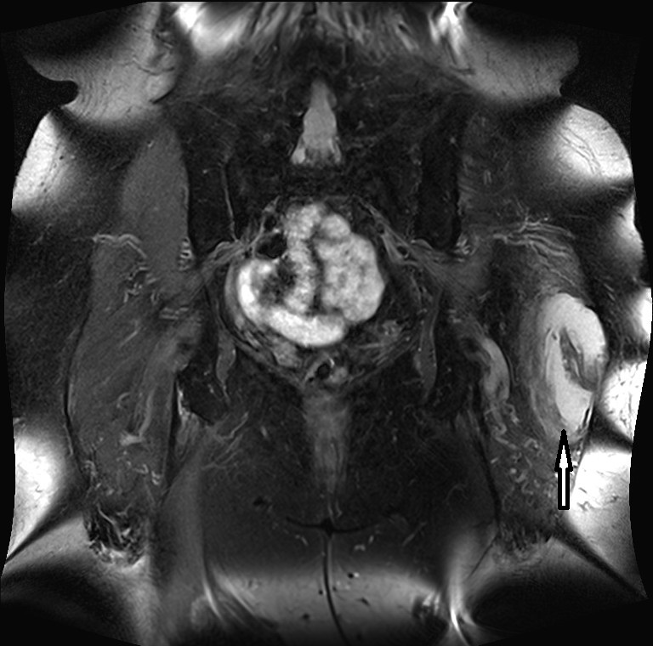

Figure 1: Proton-weighted coronal plane showing an enlarged bursa trochanterica on the left side

Lateral to the greater trochanter in the bursa trochanterica there was evidence of fluid showing homogeneous hyperintensity without sedimentation in fluid-sensitive sequences. Proton-weighted imaging revealed two nodular wall extensions in teardrop shape extending craniolaterally. These extensions measured a maximum of 1 cm at the base. In addition, at the roof of the fluid-filled cavity there was a space measuring approximately 1.5 x 0.5 cm. In the native fat-suppressed T1 turbospinecho sequence, this space-occupying lesion was partially hyperintense. This was considered to be hemosiderin. After application of gadolinium, there was a vigorous enhancement of the lining of the height. In addition, there was diffuse enhancement of the muscles in the immediate vicinity of the bursa. The hemorrhaged mass showed no enhancement of the contrast medium. In summary, the recent MRI exhibited an enlarged trochanteric bursitis with some intrabursal soft tissue formation suspicious for pigmented villo-nodular synovitis (PVNS) of the bursa trochanteric (PVNSBT) (Figure 1 [Fig. 1], Figure 2 [Fig. 2], Figure 3 [Fig. 3], Figure 4 [Fig. 4]).